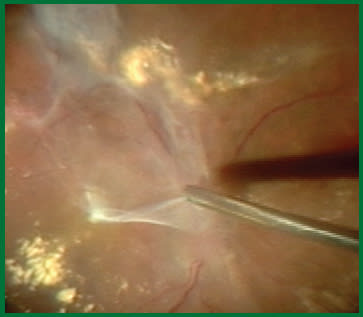

Figure 5. Viscodissection helps to lift fibrovascular tissue so it can be removed more easily with the vitrectomy probe.

Also, once inside the eye to treat a diabetic traction detachment, I try to remove all of the vitreous and the blood in the vitreous before addressing the fibrovascular tissue. This improves my view into the eye and allows me to quickly handle any new bleeding that may emerge, before clotting occurs. A strategy I use to prevent bleeding in traction/rhegmatogenous cases is to viscodissect the abnormal tissue (Figure 5). This creates a plane between it and the retina so it can be removed more easily with the vitrectomy probe. Again, as I mentioned previously, I am able to work very close to the retina in this scenario, which was unthinkable with earlier technologies.